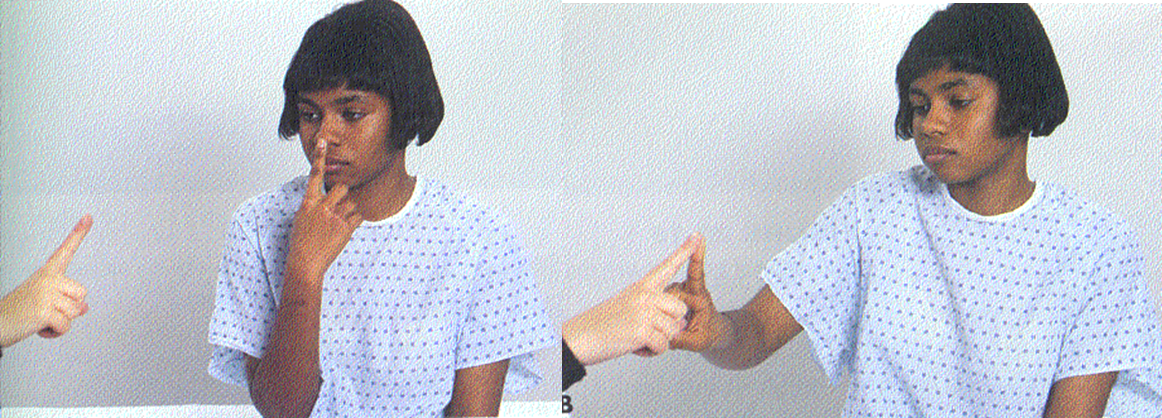

C) Fingers-nose

Finger-to-nose with moving target

Stationary finger-to-nose with eyes closed

FINGER NOSE TEST